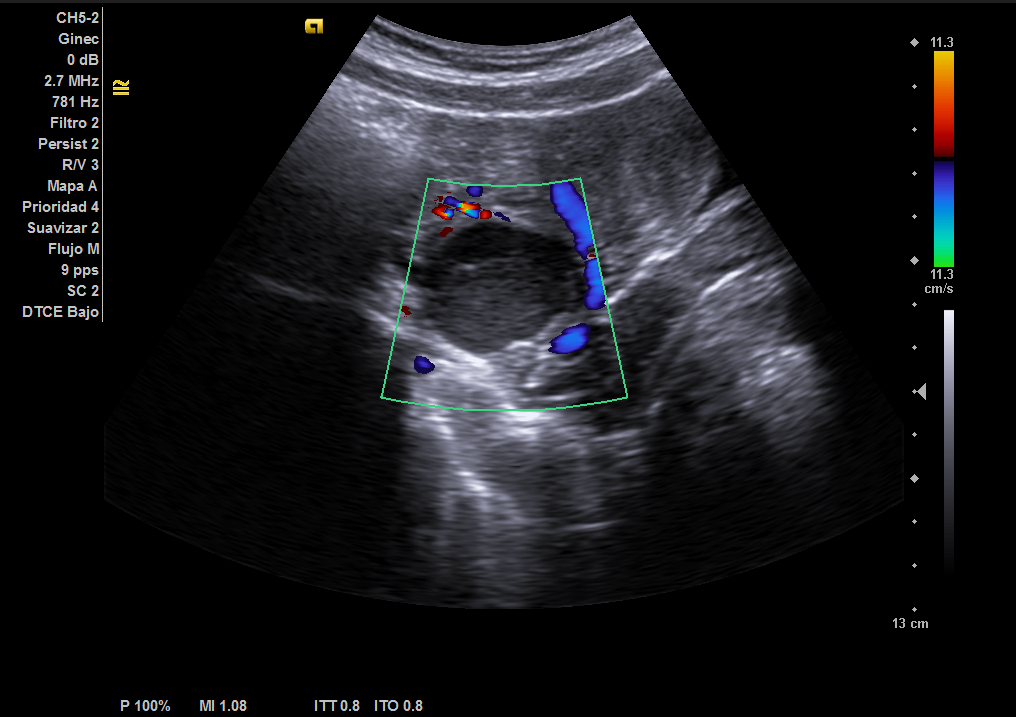

Durante la realización de una de las actividades formativas en Ecografía Clínica por parte de una Unidad Docente de formación MIR, concretamente, en el apartado práctico de la misma durante la exploración urogenital de una de las alumnas participantes, que se había prestado como modelo para la misma, se visualiza una masa anexial derecha no conocida.

Según los criterios ecográficos de IOTA, esta masa cumple con criterios ecográficos de benignidad, presentando características propias de quiste hemorrágico, y no precisando seguimiento posterior según las recomendaciones.